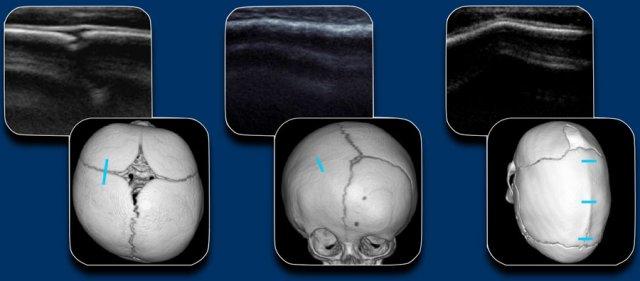

Khi nghi ngờ có dính khớp sọ sớm, phương tiện chẩn đoán hình ảnh đầu tay sẽ là siêu âm hoặc X-quang, tùy thuộc vào kinh nghiệm và sở thích của từng cơ sở y tế.

Do không có bức xạ ion hóa, siêu âm là phương pháp được ưu tiên lựa chọn.

Trong trường hợp nghi ngờ lâm sàng cao, CT 3D liều thấp được ưu tiên hơn.

Hình ảnh minh họa siêu âm của một đường khớp bình thường, hẹp đường khớp vành một bên và hẹp đường khớp dọc giữa kèm gờ xương.